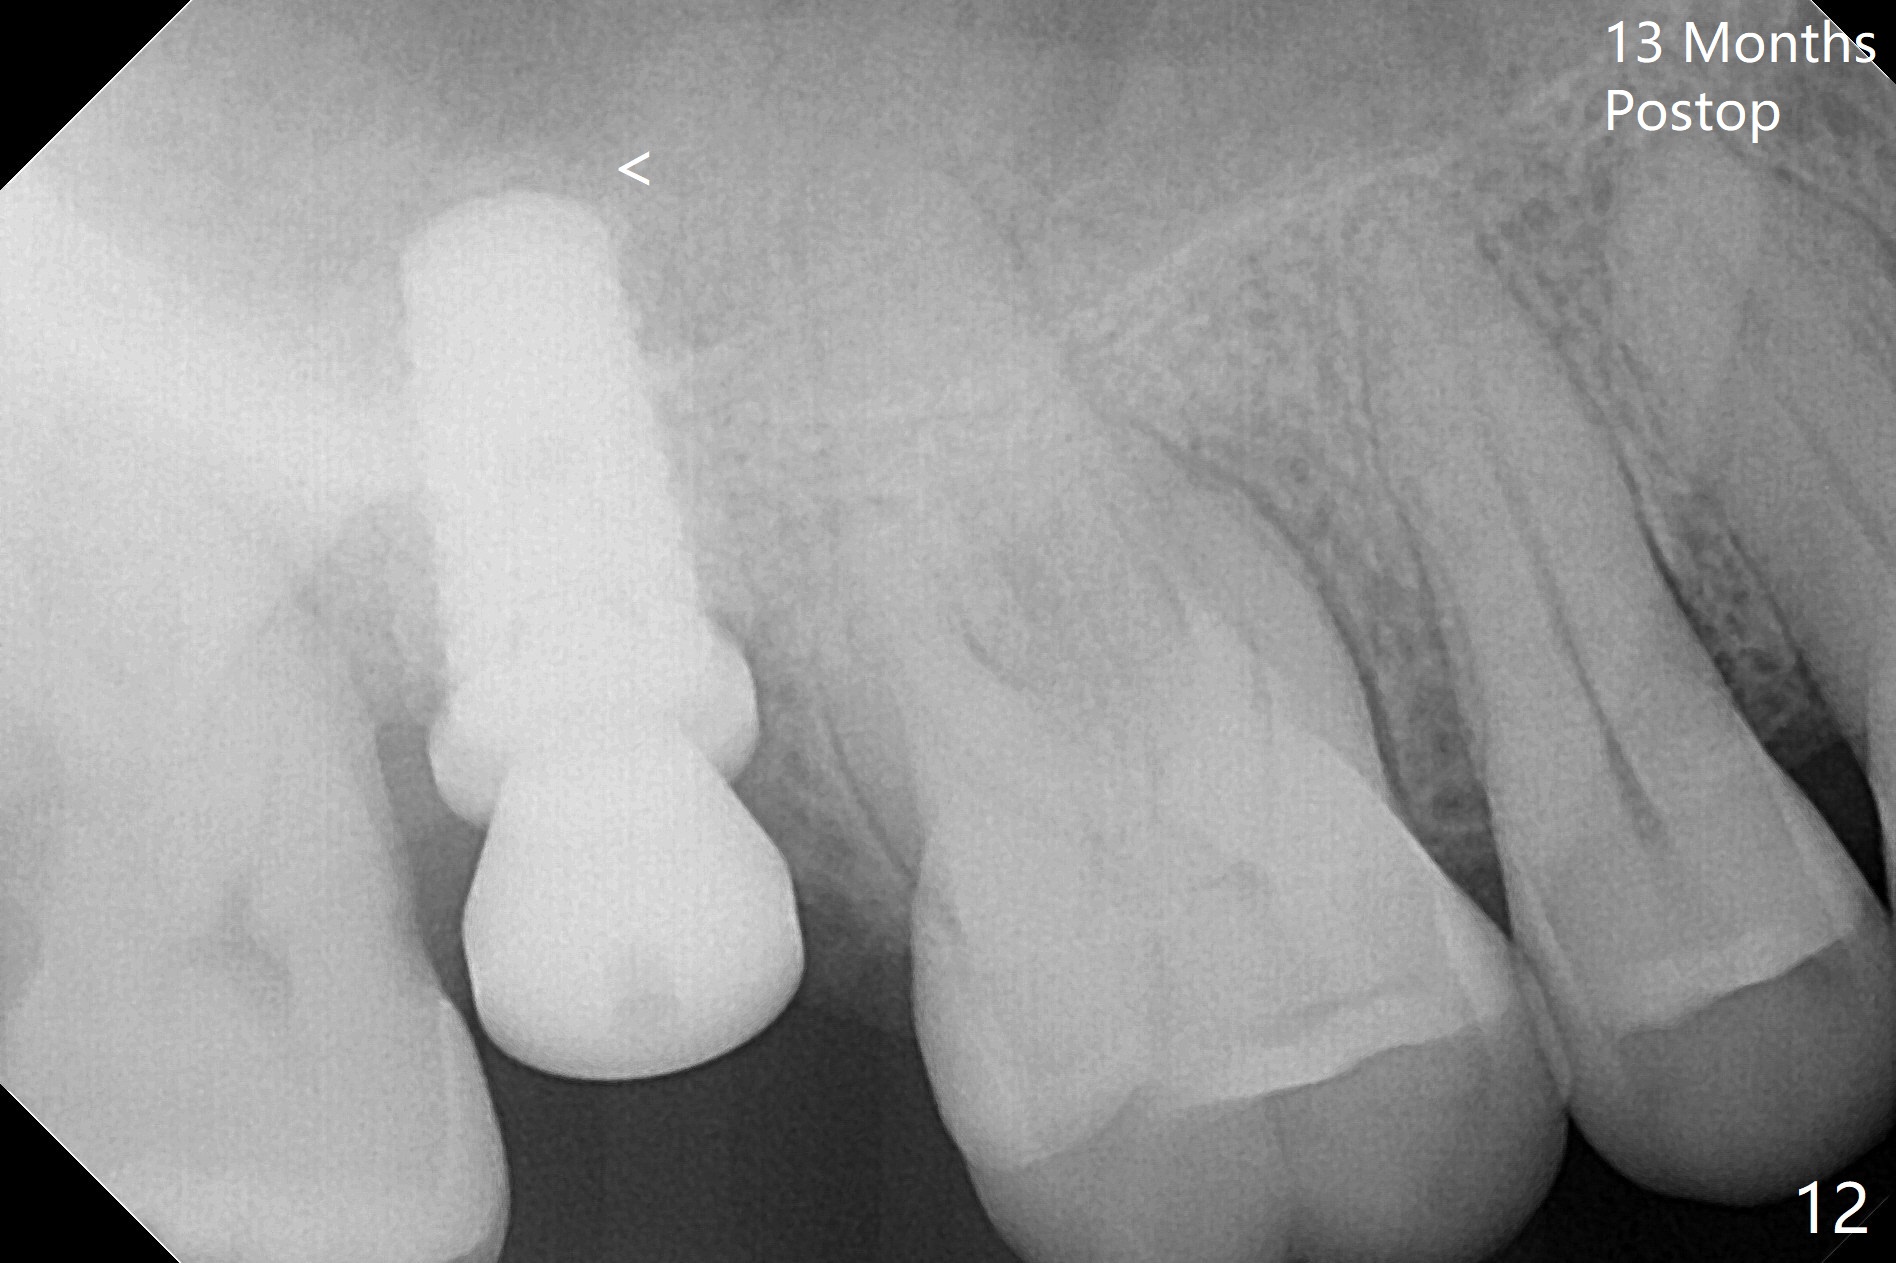

When the 59-year-old man returns for #24 implant placement, the tooth #2 is found to have crack (Fig.1,2 arrowheads), associated with buccal and palatal fistulae (*) and loss of amalgam (Fig.4 *). Abundant granulation tissue is attached to the roots of the affected tooth (Fig.3), indicating severe bone loss. There is a plateau associated with the septum and buccal sockets, which is the site of osteotomy. Magic split and 3 and 3.8 mm Magic Expanders are used to initiate osteotomy. After use of 4.3 mm Magic Drill for about 3 mm, Osteogen plug and allograft are used for sinus lift, followed by insertion of a 4.5x11 mm dummy implant (Fig.5). When a 5.5x9 mm dummy implant is placed with stability, it appears to be seated cervical (Fig.6,7). When a 6x9 mm IBS implant (definitive) is placed with a 6.5x5.5(4) mm abutment, they are seated too deep for provisional (Fig.8). The implant/abutment are removed and replaced by a 6.5x11 mm one in a shallower position; after trimming the same abutment as mentioned above (Fig.9), an immediate provisional is fabricated to keep bone graft in place. Fabrication of Tap with soft tissue markers will reduce the chance of miscalculation and waste of implants. The coronal threads of the implant are covered with bone 6 months postop (Fig.10). One month later when a permanent crown tries in, the implant is found to be loose and tender. A healing abutment is placed. Six months later, the patient returns for crown retry-in. The tooth #1 seems to have shifted mesially (Fig.11 arrow). When the abutment is placed, the implant remains tender and loose. After implant removal with a wrench, there is no granulation tissue or bony defect, including the intact sinus floor (Fig.12 <). Since the tooth #1 has deep periodontal pockets and mobility, the tooth is extracted with abundant granulation tissue. After debridement, Osteogen plug is placed in the socket of #1, while Vanilla graft is placed at the site of #2 (Fig.13 *). Three weeks later, the socket of #2 heals with exposure of Osteogen plug (Fig.14 (B: buccal)).